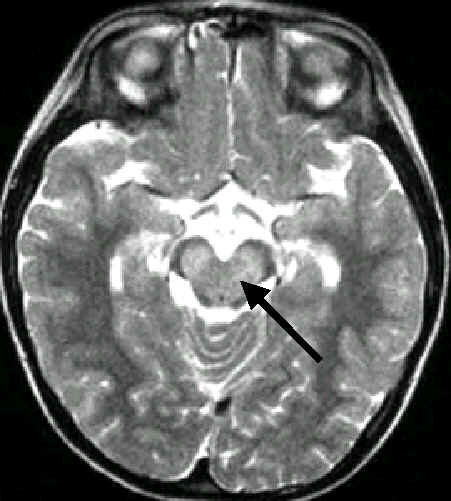

本院已從部份病童身上分離出腸病毒71型,並且利用核磁共振掃描影像

,已在兩例病情嚴重之病童身上,發現在中腦、橋腦、小腦有明顯之病變。

因此這一波的感染,腸病毒71型可能難逃關係,且主要可能因為侵犯中腦、

腦幹而造成病童出現昏迷甚至休克等現象。及早發現,及早治療,獲救機會

將提高。(小兒感染科 丘秀慧醫師)

中國醫藥學院附設醫院在這波腸病毒流行中,迄今70例有中樞神經感染的患者

中,3例出現單肢麻痺,其中2例是上肢麻痺,1例是下肢麻痺。下肢麻痺這例

是14個月大男孩,先有手足口症,5天後又因心跳加快、呼吸急促而住入加護

病房,當時磁振造影已証實他的腦幹受侵犯,小兒科醫師予以成功治療脫離危

險之後,又發現他的左下肢麻痺,磁振造影檢查發現胸椎脊髓末端脊髓灰質左

側有病變,表示受病毒侵犯(見附圖),與臨床症狀相吻合。事實上這個受侵犯

的位置正是一般小兒麻痺者脊髓被侵犯的位置,只是他被侵犯的是脊髓的一側

,因此只引起單肢麻痺。這個小男孩如我們所預料的每天都在明顯地進步中,

並已出院,他的單肢麻痺應可在一個月左右完全復原。